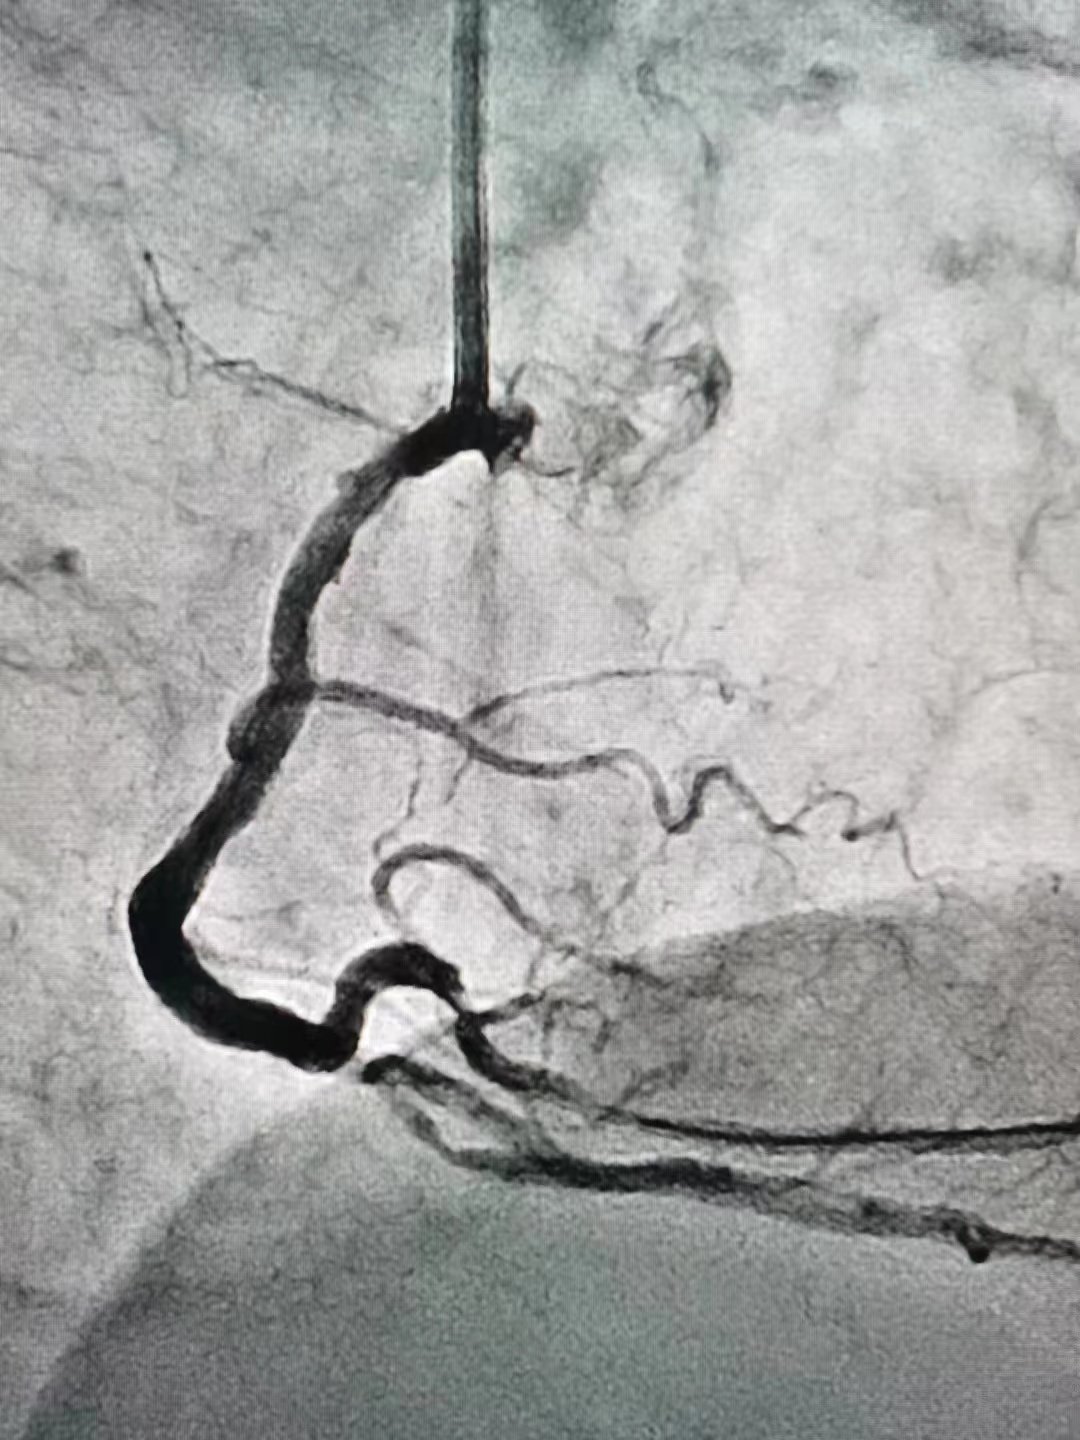

冠脉造影

冠脉造影结果:LM外膜钙化,内膜不光滑,中段狭窄90%,TIMI3级。LCX外膜钙化,内膜不光滑,TIMI3级。RCA外膜钙化,内膜不光滑,近段狭窄80%,中段狭窄90%,可见破损斑块,TIMI3级。

冠脉内介入治疗